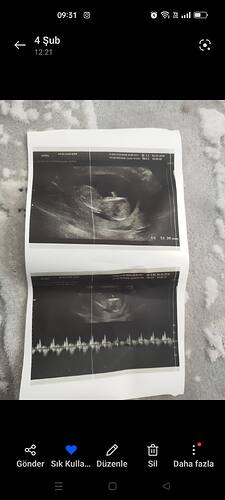

Bende atsam bakarmısınız rica etsem

Atabilirsiniz

Bu yüzde 80 erkek bence